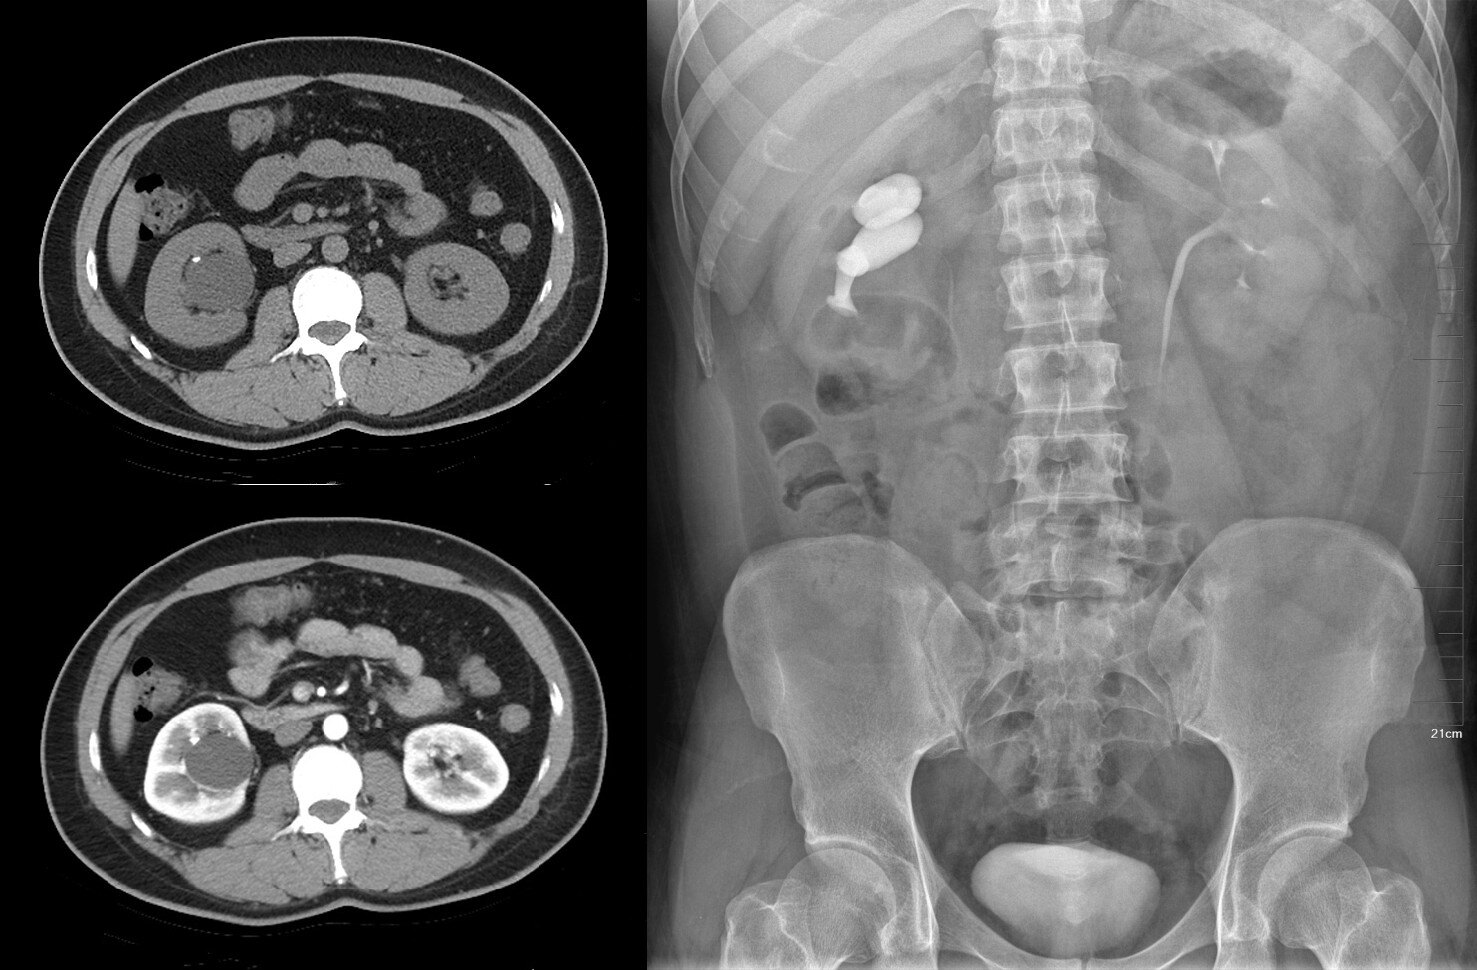

肾癌ct诊断与鉴别诊断

肾癌

罕见复杂肾癌病例分享